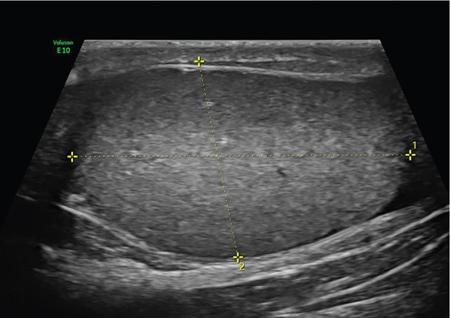

ULTRASOUND MALE PELVIS Vivek Kashyap Pelvic ultrasound is a noninvasive technique for imaging major organs in the pelvis including the bladder, prostate gland, blood vessels and bowel. It is usually the first line of investigation to evaluate the prostate and seminal vesicles. Ultrasound is a safe and reliable imaging resource to assess the pathology and guide towards appropriate treatment plan. To start pelvic ultrasound with evaluation of the shape and size of the bladder. The bladder is in the pelvis, posterior to the pubic bones. The peritoneum is seen superior to the urinary bladder and reflecting over the anterior surface. The trigone is a triangular area bounded by the two ureteric and urethral orifices. The urinary bladder has an outer loose connective tissue layer, known as subserosa which bounds the three muscular layers. The innermost is the mucosal layer. These layers should be smooth and uniform and the thickness will depend on the bladder distension. Prostate can be seen posterior to the urinary bladder when examined in transverse views. Prostate is seen at the inferior part of the urinary bladder in sagittal view (Fig. 11.1.1.1A). It should be examined in both the views. Urinary bladder neoplasms are usually seen arising from the walls of the urinary bladder, though these can be of varying shapes, usually are polypoidal and can present as solitary or multiple lesions, often seen on opposing walls of the urinary bladder, also known as ‘kissing lesions’ (Fig. 11.1.1.1B). For evaluating the bladder, it should be moderately filled. An overfilled bladder will cause patient discomfort and can compress structures posterior to it. The bladder should be scanned in the transverse and sagittal planes and prevoid volume is calculated. After micturition, the length, width and height (cm) of the bladder are recorded in sagittal and horizontal planes. The postvoid residual volume is calculated using the formula: Postvoid residual volume (PVR) = Length × Width × Height × 0.5 Normally there is no residual urine. PVR less than 50 is usually considered as insignificant. PVR volume more than 100 mL is considered significant in adults. Ureteric jets are the normal visualization of the physiological periodic efflux of urine from the distal ureter into the bladder. Ureteric jet can be appreciated by colour Doppler examination as a sudden burst of colour in the bladder that lasts for a few seconds. Bladder wall thickening is considered significant if >3 mm in a distended bladder and >5 mm in a collapsed bladder; however, it’s a good practice to fill the bladder completely before doing the investigation (Fig. 11.1.1.2). The common causes of bladder wall thickening include: Urinary bladder diverticula are examined very well on ultrasound (Fig. 11.1.1.2). Congenital diverticula, also known as Hutch diverticula are generally seen near the ureteral orifices. Acquired diverticula are generally due to bladder outlet obstruction. Bladder mucosa herniates through weak portions of the bladder walls, this may create diverticula with a narrow neck leading to urinary stasis, which may in turn cause stones, infection tumours or ureteric obstruction. These diverticula appear as an outpouching sac from the bladder and urine may be seen flowing into or out of the diverticulum. Intraluminal pathologies such as vesicle calculus are seen within the bladder, calcifications are seen in the bladder wall or in the mass lesions. Faeces, inflammatory or neoplastic bowel lesions, enlarged lymph node, masses from nerves, vessels and bones, ectopic or transplant kidney, accessory spleen can also be diagnosed from pelvic ultrasound. Ultrasound use for the male pelvis even though limited, has great importance to detect free abdominal fluid, undescended testes in the groin and hernias. Dilated urethra in posterior urethral valves, and occasionally a valve itself can be seen in real-time sonography, aided by transperineal scanning. Prevoid and postvoid volume Wall thickness Ureteric jets Size and volume Morphology of central and peripheral zone Morphology of seminal vesicles ULTRASONOGRAPHY INGUINOSCROTAL REGION V. Sivakumar Ultrasonography is the ideal noninvasive imaging modality for evaluation of scrotal abnormalities. It is capable of differentiating the most important aetiologies of acute scrotal pain and swelling, including epididymitis and testicular torsion, and is the imaging modality of choice in acute scrotal trauma. In patients presenting with palpable abnormality or scrotal swelling, ultrasonography can detect, locate and characterize both intratesticular and extratesticular masses and other abnormalities. A 12–17 MHz high-frequency linear array transducer provides excellent anatomic detail of the testicles and surrounding structures. In addition, vascular perfusion can be easily assessed using colour and spectral Doppler analysis. In most cases of scrotal disease, the combination of clinical history, physical examination and information obtained with ultrasonography is sufficient for diagnostic decision making. This review covers the normal scrotal anatomy as well as various testicular and scrotal lesions. Ultrasound is the widely used modality of choice for evaluation of scrotal abnormalities. Scrotal ultrasound is very helpful differentiating the most common causes of acute scrotal pain and swelling, including epididymoorchitis and torsion testis, and is the choice of investigation for acute scrotal trauma. Detection, localization and characterization of intratesticular and extratesticular pathologies are made easy using scrotal ultrasound. A 12–17 MHz high-frequency linear probe or transducer provides valuable anatomical information of testes and adjacent structures. Colour and spectral Doppler analysis can be used in assessing the vascular perfusion status of scrotal structures in real time. In most cases of scrotal disease, the combination of course, clinical history, clinical examination and imaging finding on ultrasound and Doppler is very essential in the diagnosis of scrotal diseases. Clinical examination sometimes leads to nonspecific signs and symptoms such as vague scrotal pain, suspicious scrotal mass or swelling. In such situations, ultrasound is useful in diagnosing and characterizing intratesticular and extratesticular pathologies as well as distinguishing benign or malignant lesions as well as identifying conditions requiring emergency surgical attention. Scrotum is a fibromuscular sac like structure divided into two hemiscrotum, right and left by a midline septum or raphe. Both the testes are located within the scrotum. The normal testicle appears like a ovoid structure with a homogeneous intermediate echogenicity and measuring approximately ~ 5 × 3 × 2 cm (craniocaudal, anteroposterior, width) (Fig. 11.1.2.1) Epididymis is elongated comma-shaped structure abutting posterior margin of testes and divided into three parts, head, body and tail. Epididymal head is seen in close relation to superior pole of testis and appears iso- to hyperechoic to the adjacent testicular parenchyma (Fig. 11.1.2.2). Epididymal body and tail can be visualized posterior to and along inferior pole of the testes and appears isoechoic to testicular parenchyma. A separate fibrous capsule called the tunica albuginea in each of the hemiscrotum encloses the testes and epididymis. This fibrous capsule can be noticed as a thin echogenic band like structure surrounding the testis on ultrasound. Tunica albuginea is covered by the tunica vaginalis, which is a remnant of processus vaginalis. It represents a closed sac of peritoneum and has two layers. The visceral layer of tunica vaginalis is seen lining the tunica albuginea of testis and is separated from the parietal layer that lines the inner aspect of the scrotal wall by minimal fluid-containing interspace. The tunica albuginea extends into the posteromedial aspect of testis to form the mediastinum testis (Fig. 11.1.2.3). It contains ducts, nerves and blood vessels. On ultrasound mediastinum is noticed as a thin echogenic band like structure. There are numerous fibrous septa extending from mediastinum testis dividing the testicle into multiple small lobules. The lobules are made of seminiferous tubules, they converge to form the tubuli recti, which are the testicular ducts that open into the rete testis. In around 20% of population, the rete testis can be visualized as a hypoechoic area adjoining the mediastinum testis. Efferent ductules coming out of rete testis can be seen draining into the epididymal head. From epididymal head, the ducts converge into a single duct in the epididymal body and exit the epididymal tail as the vas deferens. The vas deferens runs along the contents of spermatic cord and courses superiorly within the inguinal canal. The spermatic cord contains nerves, testicular artery, deferential artery, cremasteric artery, lymphatic ducts and the pampiniform venous plexus. On ultrasound the spermatic cord appears as an echogenic band like structure within the inguinal canal. The major vascular supply to the testes is by the paired testicular arteries which arise from the abdominal aorta. The testicular artery after entering into the tunica albuginea branches into capsular arteries and recurrent rami branches which then courses centrifugally into the mediastinum. A collateral circulation comprising of deferential artery and the cremasteric artery is also seen. Arterial supply to the remaining parts of the scrotum is from the pudendal arteries, which arise from the internal iliac artery. Anatomic relationships of the vascular structures within the spermatic cord are important and alteration in this normal relationship is associated with few pathologies. High insertion of tunica vaginalis to the spermatic cord, the bell-and-clapper deformity leaves the testes to rotate freely within the tunica and can lead to intravaginal testicular torsion. The pampiniform venous plexus continues as the testicular vein in the deep inguinal canal. The right testicular vein drains directly into the inferior vena cava (IVC) whereas the left testicular vein drains into the IVC via the left renal vein. Epididymal and testicular appendages usually represent embryologic remnants. They are better visualized in ultrasound in the presence of a hydrocele. The appendix of testis (hydatid of Morgagni) can be visualized as an isoechoic, oval structure between the epididymis and testis (Fig. 11.1.2.4). An appendix of epididymis is a pedunculated structure arising from the epididymal head, which is also isoechoic to testicular tissue. Ultrasound of the scrotum includes both greyscale and colour Doppler evaluation of testicles, epididymis on both sides and the scrotum. Spectral Doppler evaluation can be used to demonstrate normal waveforms in the testicular artery and vein. For scanning a high frequency, broad bandwidth 17–5 MHz or 12–5 MHz linear array transducer is used. With the help of a towel placed under the scrotum the testicles and scrotum are elevated. With another towel the patient retracts and covers his penis. Initially with a side-to-side large-field imaging both testes are demonstrated using both greyscale and Doppler techniques. Echogenicity and perfusion of each testis is examined. Each testis is imaged longitudinally in medial, mid, lateral portions and transversely in upper, mid and lower pole regions. Three-dimensional (3D) measurement of each testicle is taken (length, width and height). Epididymis evaluation includes longitudinal and transverse imaging including head, body and tail. Colour Doppler study of testes and epididymis is done on both sides and status of capsular and centripetal arteries assessed and documented. Spectral waveform of both arterial and venous flow is documented on each side. Optimization of colour and spectral Doppler analysis is done to clearly depict low velocity venous flow. Colour Doppler imaging in various planes and comparison with contralateral asymptomatic testis is done in specific evaluation for testicular torsion. Scrotal survey should be done for extratesticular findings such as hydrocele, varicocele or calcification/scrotolith. The pampiniform plexus of veins should be evaluated for the diameter and its augmentation on standing position or Valsalva manoeuvre. Scrotal wall should be assessed for thickening and oedema. Extratesticular and intratesticular pathologies, either focal or diffuse should be identified and characterized using grey scale and Doppler imaging techniques appropriately. Focal lesions should also be measured three dimensionally. Presence of solid, cystic, calcific, complex cystic areas in the lesion should be characterized. Labelling of the lesion/images in respect to location (upper, middle or lower), orientation (longitudinal and transverse) and position of the patient (supine, decubitus and standing) is done. Labelling of the lesion/images during specific manoeuvres such as Valsalva should also be done. For scanning a high frequency, broad bandwidth 17–5 MHz or 12–5 MHz linear array transducer is used. Initially with a side-to-side large-field imaging both testes are demonstrated using both greyscale and Doppler techniques. Echogenicity and perfusion of each testis and epididymis should be examined. Each testis is imaged longitudinally in medial, mid, lateral portions and transversely in upper, mid and lower pole regions. Epididymis evaluation includes longitudinal and transverse imaging including head, body and tail. Spectral waveform of both arterial and venous flow is documented on each side. Ultrasound and colour Doppler are the first-line imaging modality for acute or chronic scrotal pathologies. Ultrasound is a safe and reliable imaging modality for demonstration of scrotal anatomy, localization of testicular pathologies and for assessing the vascularity. Since most of the testicular pathologies have characteristic ultrasound appearance, ultrasonography is able to clearly guide patient management and prevent unnecessary surgery. TRANSRECTAL ULTRASOUND OF PROSTATE Vivek Kashyap Carcinoma prostate is the second most common cancer in the world and the sixth leading cause of cancer death in men. The worldwide burden of prostatic cancer is estimated to touch 1.7 million new cases and 499,000 deaths by 2030. The prostate is an unpaired glandular organ. The average dimensions in a healthy young adult is 3.75–4.00 × 2.5–3.00 × 3.1–3.8 cm (w × h × l) and the volume ranges from 20–25 cm3. It produces the prostate-specific antigen (PSA) a glycoprotein which is an ingredient of the semen and is responsible for liquefying semen. The prostate has endocrine properties as it produces prostaglandins E, F and A, spermidine and spermine. It is also the place of the conversion of testosterone into dihydrotestosterone under the influence of the 5-α-reductase enzyme. COMMON INDICATIONS FOR A TRANSRECTAL ULTRASOUND (TRUS) OF PROSTATE Assessment of prostate size Abnormal growth within the prostate Male infertility Elevated PSA levels Detecting disorders within the prostate Micturating difficulties Because ultrasound provides real-time images, it can be used to guide biopsies which may be necessary, FNAC or tissue biopsy as well as brachytherapy seed placements. Transrectal US is a widely used clinical imaging method. For confirming the diagnosis of prostatic cancer, a systematic needle biopsy with US guidance is the diagnostic test of choice (Fig. 11.1.3.1). To understand the images produced by transrectal US, it is important to understand the zonal anatomy of the prostate gland. The outer zone is the peripheral zone, inner to it the transitional zone, then central zone and periurethral zone. The peripheral zone is the largest, containing almost 70% of the prostatic tissue and is the site of most prostatic cancers. It is separated from inner zones by a surgical capsule which may be seen as hyperechogenic line The transitional zone is much smaller (about 5%) and is seen as two small glandular areas such as saddle bags adjacent to proximal urethral segment. The central zone constitutes almost 25%–30% of the total gland size. The ducts of vas deferens and seminal vesicles pass through this zone. This zone shows only about 5% incidence of cancers and appears relatively resistant to diseases. The periurethral zone is only about 1% and encircles the urethra. The commonest features of benign prostatic hyperplasia are hypoechoic enlargement of inner zone. Other features could be calcifications along with diffuse or well-circumscribed rounded hypoechoic or hyperechoic nodules along with degenerative or retention cysts (Fig. 11.1.3.2A,B). Well-circumscribed hypoechoic nodules arising in the transitional zone may become so large that they distort the gland and appear to be in the peripheral zone and these are invariably benign. In cases of hyperplastic nodules occurring in the peripheral zone, they will appear as firm to hard nodules and should undergo a biopsy. We must remember that prostatic enlargement may not correlate with urinary symptoms in all cases, therefore any urinary dysfunction calls for evaluation of the prostate, bladder, urethra, spine and CNS. Transvesicle ultrasound is done to evaluate prostate size, median lobe, bladder trabeculations, diverticula, tumours or calculi. Patients who have had TURP done before will invariably show a defect in the gland. However, the size of the defect will not always correlate with the amount of tissue removed during the procedure, nor does it correlate well with the success of the procedure. This is a condition of inflammation of the prostate and seminal vesicles. The prostate may appear normal in prostatitis or there may be a focal mass, ejaculatory duct calcification, irregularity or thickening of the capsule, periurethral glandular irregularity, dilated periprostatic veins and distended seminal vesicles. Chronic granulomatous prostatitis can present as diffuse large or small hypoechoic zones or a solitary hypoechoic lesion. The examination is generally painful and colour Doppler may show a very vascular focus (Fig. 11.1.3.3A). If we see a hypoechoic mass within the prostate with or without internal echoes may be an abscess. Common ones are degenerative or retention cysts in hyperplastic nodules. These are generally symptomless, unless they become large (Fig. 11.1.3.3B). Prostatic utricle cysts are in the midline and are caused by dilatation of prostatic utricle. These can be associated with unilateral renal agenesis and rarely contain spermatozoa. Other type of cysts seen are Mullerian duct cyst which are a little lateral and are also tear drop and do not contain spermatozoa. Ejaculatory duct cysts are small and could be a small diverticulum of the ejaculatory duct or an obstruction. These can be fusiform in shape with pointed ends and contain spermatozoa. These are associated with infertility. Seminal vesicle cysts are another type, which could be large and solitary, associated with ipsilateral renal agenesis sometimes. In cases of male infertility, transrectal sonography has an important role in assessment of causes of azoospermia for ejaculatory duct obstruction or anomalies (about 1%–2%) Seminal vesicles, dilated ejaculatory ducts and midline cysts can suggest obstruction. There is a strong association of absence of vas with cystic fibrosis. The results of transrectal scanning in infertile men with azoospermia can be normal appearance (25%), bilateral absence of vas deferens (34%), bilateral occlusion of the vas, seminal vesicles or ejaculatory ducts by calcification or fibrosis (16%), unilateral absence of vas (11%), obstructing cysts (9%), ductal obstruction due to calculi (4%). Some of these causes, more so in distal two-thirds could be surgically correctable and therefore it is essential that careful evaluation is done. Haematospermia is blood in the semen. This could be acute (red in colour) or dark brown (old blood). Nonspecific inflammation of the prostate or seminal structures is the most common cause, resolving on its own after some time. We should exclude tumours or infection of prostate or bladder. Transrectal scanning can detect calculi or cysts in the seminal vesicles or ejaculatory ducts (Fig. 11.1.3.4). Other causes includes vascular malformation or sometimes following a prostatic biopsy. Ultrasound elastography is an imaging technique for mapping tissue stiffness of the prostate gland. Two elastography techniques that have developed are strain technique, and second, shear wave technique. The tissue stiffness information provided by US elastography can improve the detection rate of prostate malignancy and provide guidance for biopsy. Prostate elastography has high sensitivity for detecting prostate malignancy and shows high negative predictive values, ensuring that few malignant lesions will be missed. Transrectal US has been used for local staging of prostate cancer in some studies but is generally considered insufficient. Extracapsular extension (ECE) can be demonstrated by the bulging or irregularity of the capsule adjacent to a hypoechoic lesion. Seminal vesicle invasion (SVI) is diagnosed by demonstrating the extension of a lesion at the base of the prostate into a seminal vesicle. Solid hypoechoic lesions within the seminal vesicles or asymmetry of the seminal vesicles are indirect indicators of disease extension. Additional transrectal US-guided biopsies of the seminal vesicles can be performed when extra prostatic extension into the seminal vesicles is suspected. Studies performed in the 1980s showed when cancers are larger (stage T3) and more readily palpated, sensitivity for detecting ECE and SVI by transrectal US was more than 80%. With advent of colour duplex and power Doppler US, there has been renewed interest in the use of transrectal US to identify cancer in hyper vascular areas, with only modest improvements in sensitivity and specificity. Transrectal US continues to play an important role in therapy for directing brachytherapy seeds into the accurate location within the prostate. Cryotherapy and focal ablation of the prostate cancer also requires transrectal US guidance. Future developments in transrectal US may include the utilization of microbubble contrast agents and targeted imaging. Microbubbles coated with surface ligands that preferentially target tumour neovascularity can be used. Because of the large size of these bubbles (1 m), these agents can provide information about large-vessel microvascularity which can be useful in detecting cancer; however, if in future smaller-size microbubbles are available, they can further improve detection. Seminal vesicles have symmetric appearance and lie cephalic to the prostate and posterior to the bladder. They have a typical ‘bow-tie’ appearance in transverse scans, and a club or tennis-racket shape in longitudinal scan. They show homogenously fine echoes but less echogenic than prostate. Volume of seminal vesicles tends to shrink after the fifth decade. TRUS provides excellent anatomical details of seminal vesical and ejaculatory ducts. TRUS helps to diagnose calculi in seminal vesicle or ejaculatory duct. Also TRUS provides high-resolution imaging of the prostate, seminal vesicles and vas deferens and is the investigation modality of choice in diagnosing congenital and acquired abnormalities implicated in the cause of obstructive azoospermia. USG FEMALE PELVIS M. Alamelu Ultrasound is a noninvasive, easily available and informative investigation. A skilfully done and well-interpreted ultrasonogram image usually obviates the need to proceed to additional expensive and composite cross-sectional imaging tests. Ultrasound is high-frequency sound waves (20 kHz), inaudible to human that can be safely transmitted into human body to scan the tissues. Images produced in ultrasound depend on the mechanical properties of tissues and their distance from the source of the sound as it will differentially affect the energy of the sound waves (Table 11.1.4.1). As the frequency of the transducer scan-head increases, the resolution increases and penetration into the body tissue decreases. The piezoelectric crystals convert electric energy into mechanical energy and sound waves are produced. Pelvic pain Pelvic masses Dysmenorrhea (painful menses) Amenorrhea Abnormal uterine bleeding Follow-up of previously detected abnormality Infertility Pelvic infection Evaluation after pelvic surgery, delivery or abortion To localize intrauterine device (IUD) Screening for genital tract malignancy in high-risk patients Pelvic organ prolapse The transducer is placed longitudinally over the adequately distended bladder, the gain settings to be adjusted for optimal visualization (Fig. 11.1.4.1). Scanning is to begin longitudinally from midline between umbilicus and pubic symphysis, angulated to the sides, moved laterally to both right and left side (Fig. 11.1.4.2). Next, scan transversely beginning from pubic symphysis down to umbilicus upwards (Fig. 11.1.4.3). If needed, patient can be asked to turn obliquely (30–40 degrees) for evaluation of ovaries and adnexa (Fig. 11.1.4.4). The following should be assessed: The overall length of uterus is evaluated in the sagittal view from fundus to cervix (to the external os, if seen). The length can either be measured as a straight line from fundus to cervix by using the outer-to-outer technique or can be measured from fundus of uterus along the endometrial lining and endocervical canal using the outer-to-outer technique (Fig. 11.1.4.5). The anteroposterior measurement of the uterus is made in the sagittal view from its anterior to posterior uterine walls. The maximum width can be measured in the transverse or coronal plain. The cervical component should be excluded from uterine length measurement for volumetric assessment of uterine corpus. The neonatal uterus, with exposure of maternal hormones is well depicted with US. The uterus is more narrower and shorter, with a mean length of 3 cm in infants of 4–12 months. Cervix attains a tubular shape and is proportionate to the uterine body. After 1 year of age, uterine length gradually increases and rapid growth occurs as the girls approach puberty. The mean uterine length 3 cm or less for young girls, 3–4.5 cm for prepubertal girls and 5–8 cm for pubertal girls. During puberty, the uterine body becomes more thicker and rounded, pear shaped, with a ratio of uterine body-to-cervix – 1.5:1, an appearance similar to that in women of reproductive age (Table 11.1.4.2). Source: J.E. Langer, E.R. Oliver, A.S. Lev-Toaff, B.G. Coleman, Imaging of the Female Pelvis through the life cycle, Radiographics 32 (2012) 1575–1597. H.J. Paltiel, A. Phelps, US of the pediatric female pelvis, Radiology 270 (2014) 644–657. Depending on the extent of the urinary bladder distension the normal uterus assumes a number of positions. Depending on the relationship of the angle of the long axis of the uterine body to the long axis of the cervix (flexion) and the long axis of the uterus to the long axis of the vagina (version) various positions are described. The most common position for uterus is in anteversion and anteflexion (Fig. 11.1.4.6). When the uterus is positioned in retroversion or retroflexion, it will be difficult to image transabdominally in most cases and is imaged well with an endovaginal transducer. Following every delivery, the uterus of parous women becomes more thick and round. After caesarean delivery, the uterus typically appears more elongated with variable deformity or thinning at the site of the lower uterine incision. The postmenopausal uterus is atrophied and small. The reduction in uterine size is most rapid during the first decade after menopause. The range can vary between 3.5 and 6.5 cm in length and 1.2 and 1.8 cm in anteroposterior dimensions. The endometrium should be assessed for the thickness, presence of focal abnormalities, its echogenicity, and the characteristics of fluid or masses in the cavity. The endometrium has a variable echogenicity, depending on its water content and the cellular density, that varies with the hormonal status of the patient. Neonatal uterus – The endometrium appears as echogenic line and endometrial fluid is often seen, due to residual effect of maternal hormones. The endometrium becomes less obvious, a thin echogenic line seen centrally in only 50% of girls of prepubertal age. The postpubertal endometrium is easily visible with transabdominal US and varies in thickness with the phases of the menstrual cycle. The thickness of endometrium correlates with the histologic changes to the estrogenic stimulation. The endometrium has a trilaminar appearance in preovulatory phase of menstrual cycle, then thickness becomes homogeneous after ovulation. The thin central hyperechoic line is not an endometrial layer it represents the interface between the anterior and posterior endometrial aspects. It should demonstrate as a continuous line on imaging parallel to the long axis of the uterus. Disruption of the central echogenic line, or any heterogeneity of the endometrium, indicates an underlying intracavitary lesion such as polyp, myoma or adhesion (Fig. 11.1.4.7). Progressively increasing echogenicity of the functional zone (compactum and spongiosum) seen with completion of the preovulatory phase and during the secretory phase. The homogeneously echogenic endometrium of the secretory phase poses difficulty in visualization of the central interface. For this reason, assessment of the focal abnormalities in endometrium is best done in the early phase of the menstrual cycle. The thickest part of the endometrium to be measured perpendicular to its longitudinal plane in the anteroposterior diameter, using the outer-to-outer technique, from echogenic to echogenic borders. The endometrial thickness is correctly measured from the anterior endometrial–myometrial interface to the posterior endometrial–myometrial interface. The adjacent myometrium (hypoechoic) and fluid in the cavity should be excluded in the measurements. The junctional zone thickness can be up to 12 mm (Fig. 11.1.4.8). In the women taking oral contraceptive pills or using other hormonal contraceptives, such as progesterone-releasing intrauterine devices, the endometrium is generally thin throughout the entire menstrual cycle. If the patient has an IUD, its location should be documented. Sonohysterography is an effective adjunct to further clarify an abnormally thickened or an incompletely visualized endometrium. The normal myometrium has three layers. The innermost layer is thin, relatively hypovascular and hypoechoic and is referred as the subendometrial halo. The next is the intermediate layer. It is the thickest layer and has uniform echotexture. The outer layer is also thin and slightly hypoechoic. The outer and the intermediate layer is separated by the arcuate vessels. These arteries again branch into radial arteries which penetrate through the intermediate layer and reach the inner layer. In some women the arcuate vessels (the veins) can be prominent and mimic cystic changes. During the reproductive ages, the normal uterine myometrium has homogeneous echogenicity with smooth margins. The nongravid uterus can demonstrates myometrial contractions, directed from the cervix to the fundus in the periovulatory phase, presumably to promote sperm transport, have been shown to have higher rates of successful fertilization compared to women with uncoordinated or absent wave activity. Postpartum uterus – the arcuate arteries undergo calcification, which can be seen earlier in diabetic women. This is a part of normal aging process. At times, small hyperechogenic foci are seen in inner myometrium, a few millimetres in size and nonshadowng in appearance, which represent dystrophic calcifications and have no clinical significance. The myometrium and cervix should be analysed for contour changes, echogenicity, masses, cysts and the symmetry between its anterior and posterior segments. The size and location of any pathological lesions should be measured in at least two dimensions. The normal postpartum uterus: The appearance of cervix varies with age of female. The cervix can be visualized as cylindrical-shaped structure on sagittal views and round/oval on coronal view. An echogenic central line denotes the interface between the two mucosal layers. Endocervical canal is 2–4 mm in single-layer thickness and in the centre it has a small amount of anechoic fluid or mucus. The plicae palmatae appear as serrations in the mucosa due to compact folds. The cervical stroma usually has similar echogenicity to myometrium and may demonstrate a narrow hypoechoic submucosal zone. Colour Doppler US shows little or no vascularity in the cervix. US beam is swept through the entire length of the cervix, from the internal os through the external os and upper vagina and laterally through the cervix including the bilateral parametrial and other adjacent pelvic tissues. This provides better, delineation of the cervical borders and the extent of any lesions. In case of any abnormality in the cervix identified at US, use of transducer pressure is extremely beneficial to determine if the lesion is located in the endocervical canal is arising from the stroma or from the cavity, particularly in case of a pedunculated intracavitary myoma or pedunculated polyp. On application of transducer pressure over the cervix, the intracavitary lesion may show mobility if a lesion is from the cavity mucosa, whereas lesions arising from the cervical stroma will be fixed in position despite the transducer pressure. The neonatal cervix is disproportionately large and bulbous on imaging. With increasing ages, the cervix becomes proportionate to the uterine body, producing a tubular shape. The branches of the uterine arteries can be identified on both sides of the cervix at colour Doppler flow imaging. The vagina seen as a collapsed tubular structure, distal to the uterine cervix and inferior to the urinary bladder. Caution: overdistension of the urinary bladder may cause urine accumulation in the vagina, misinterpreted for vaginal cysts. The presence of tampons or menstrual blood should also be looked. The adnexa include the ovaries, fallopian tubes, supporting ligaments and peritoneal folds of the lateral pelvis and the blood vessels. The adnexal mass lesions to be analysed for its position, relationship to the ovaries and uterus, size, shape, sonographic characteristics. The ovaries are demonstrated by scanning in transverse or longitudinal planes. They are seen lateral to the uterine corpus. The position of the ovary varies with the length of the infundibulopelvic ligament, presence of adhesions and any other anatomic abnormalities that displaces the ovaries. In neonates, the ovaries generally are easily imaged transabdominally as they are located above the true pelvis. As the child grows, the ovaries are embedded deeper in the pelvis, adjacent to the uterus. Ovarian size is to be measured in three dimensions (longitudinal, transverse and anteroposterior diameters) on views obtained in two orthogonal planes for the calculation of ovarian volume. Normal ovarian volume: simplified formula for volume calculation is 0.5 × length × width × thickness (Table 11.1.4.3). Follicles in ovaries in women of reproductive age can be demonstrated as echo-sparse, well-circumscribed areas within the ovarian stroma with varying sizes between 5 and 20 mm. Follicles are simple cysts with size of 9 mm or less. Ovarian mimics: The addition of 3D ultrasound is used to differentiate ovarian multiseptated cysts from hydosalpinges. Fallopian tubes are tubular structures extending from posterosuperior aspect of the uterine fundus. They open into the peritoneal cavity. Bilateral tubes are located in the superior edge of the broad ligament. They are 10–12 cm in length and 1–4 mm in diameter. A fallopian tube has four anatomic segments. The interstitial or intramural segment is located at the uterine cornua, within the myometrium. The isthmic segment is the narrowest portion of the fallopian tube. The ampullary segment is closer to the ovary, and constitutes around one-half of its total length. The infundibulum is funnel-shaped lateral most segment. The free edge of fallopian tube is composed of around 25 finger-like projections, called fimbriae. The fimbriae are suspended over the ovary and capture the ovum after its release. The fallopian tube is difficult to visualize in its normal state in USG. Fallopian tubes are frequently visualized in pathological conditions such as hydrosalpinx or neoplasm, the tube may be more clearly defined. Transvaginal ultrasonography is a better imaging modality for tubal visualization. The urinary bladder usually is a landmark for anatomic orientation in transvaginal and transabdominal scanning. Overdistension of the bladder will displace the uterus too posteriorly to hinder adequate imaging and also the patient will experience gratuitous discomfort. Conversely, in case of insufficient bladder filling, the posterior uterine wall or fundal lesions can be missed. Caution: a full bladder mimics a unilocular, anechoic pelvis cyst. In doubt cases, a postvoid scan is to be suggested for definitive evaluation. The bilateral urethrovesical junction and the distal urethra can be visualized in an adequately filled bladder. The cul-de-sac is posterior to the uterus and is to be evaluated for the presence of free fluid or loculated fluid and any mass lesions. Minimal free fluid (usually less than 1 cm in thickness) in the cul-de-sac is considered an unremarkable finding in girls of prepubertal ages and women of reproductive age. Artefacts are echoes that are falsely imaged without a corresponding anatomical structure (Fig. 11.1.4.9).